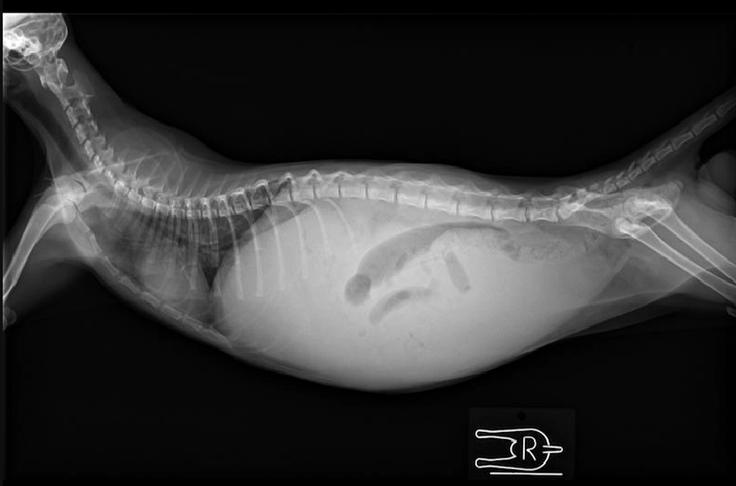

これがその時のお腹のレントゲン写真です。

お腹が白く映っており、他の臓器が見えなくなっています。白い部分は全て腹水です。

熱が40.6度あり、お腹の注射を打つと黄色い液体が出てきました。これはFIPの典型的な症状なので、ちゃんとした検査結果は後日出るけれど、ほぼFIPで間違いないだろうということでした。FIPには有効な治療法がないため、抗炎症剤を打ち、免疫力を高める方法しかないと言われ、抗炎症剤のインターフェロンを打ってもらいました。これから5日間、ステロイドやインターフェロンを打って改善が見られなければ、覚悟した方がいい。ほとんどの場合、改善がみられることはない言われました。